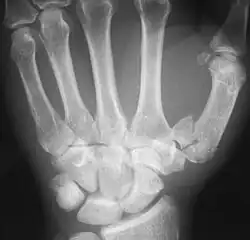

The first metacarpal (Left)

The first metacarpal bone or the metacarpal bone of the thumb is the first bone proximal to the thumb. It is connected to the trapezium of the carpus at the first carpometacarpal joint and to the proximal thumb phalanx at the first metacarpophalangeal joint.

The first metacarpal bone is short and thick with a shaft thicker and broader than those of the other metacarpal bones. Its narrow shaft connects its widened base and rounded head; the former consisting of a thick cortical bone surrounding the open medullary canal; the latter two consisting of cancellous bone surrounded by a thin cortical shell. [1]